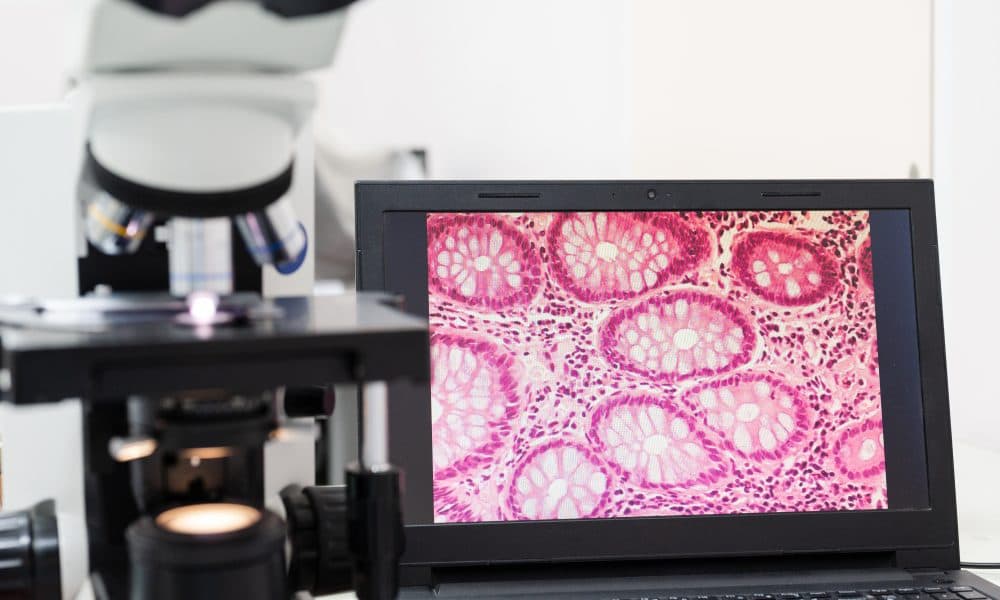

Scientists have trained an AI neural network to detect anomalies in medical images to assist physicians in sifting through countless scans in search of pathologies. Image anomaly detection is a task that comes up in data analysis in many industries. Medical scans, however, pose a particular challenge. It is way easier for algorithms to find, say, a car with [...]